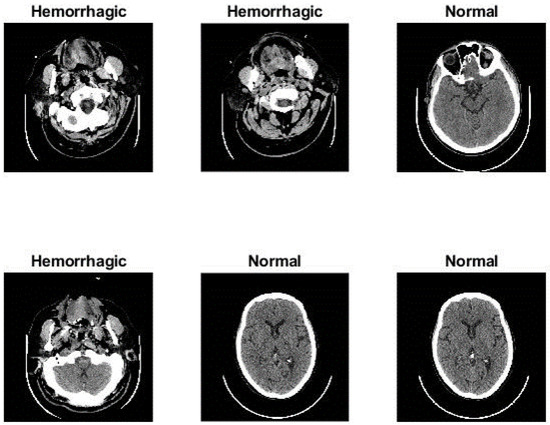

3.1. Description of the Dataset